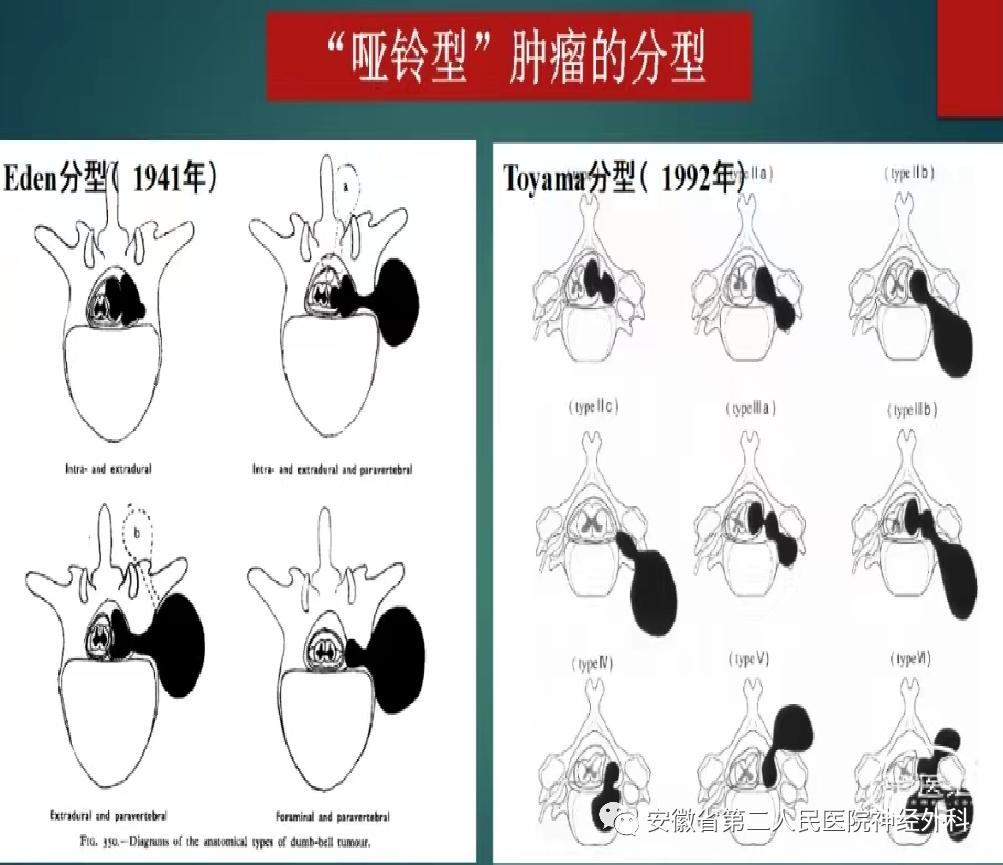

C4水平椎管内外“哑铃型”肿瘤

术前评估肿瘤类型并制定手术策略

术前拟定手术方案

患者肿瘤位于高颈段肿瘤,分型为IIb,起源于椎管内神经根并向外生长,手术风险和难度较高,同时合并多阶段颈椎椎间盘突出,术前讨论:考虑同时处理肿瘤和多阶段椎间盘,手术时间长、创伤大、风险高,本次手术拟定先行切除肿瘤+椎板减压,后期视病情行二期颈椎间盘突出手术,手术方案拟在神经电生理监测下经颈前外侧椎间孔入路+备后正中半椎板联合入路切除肿瘤。